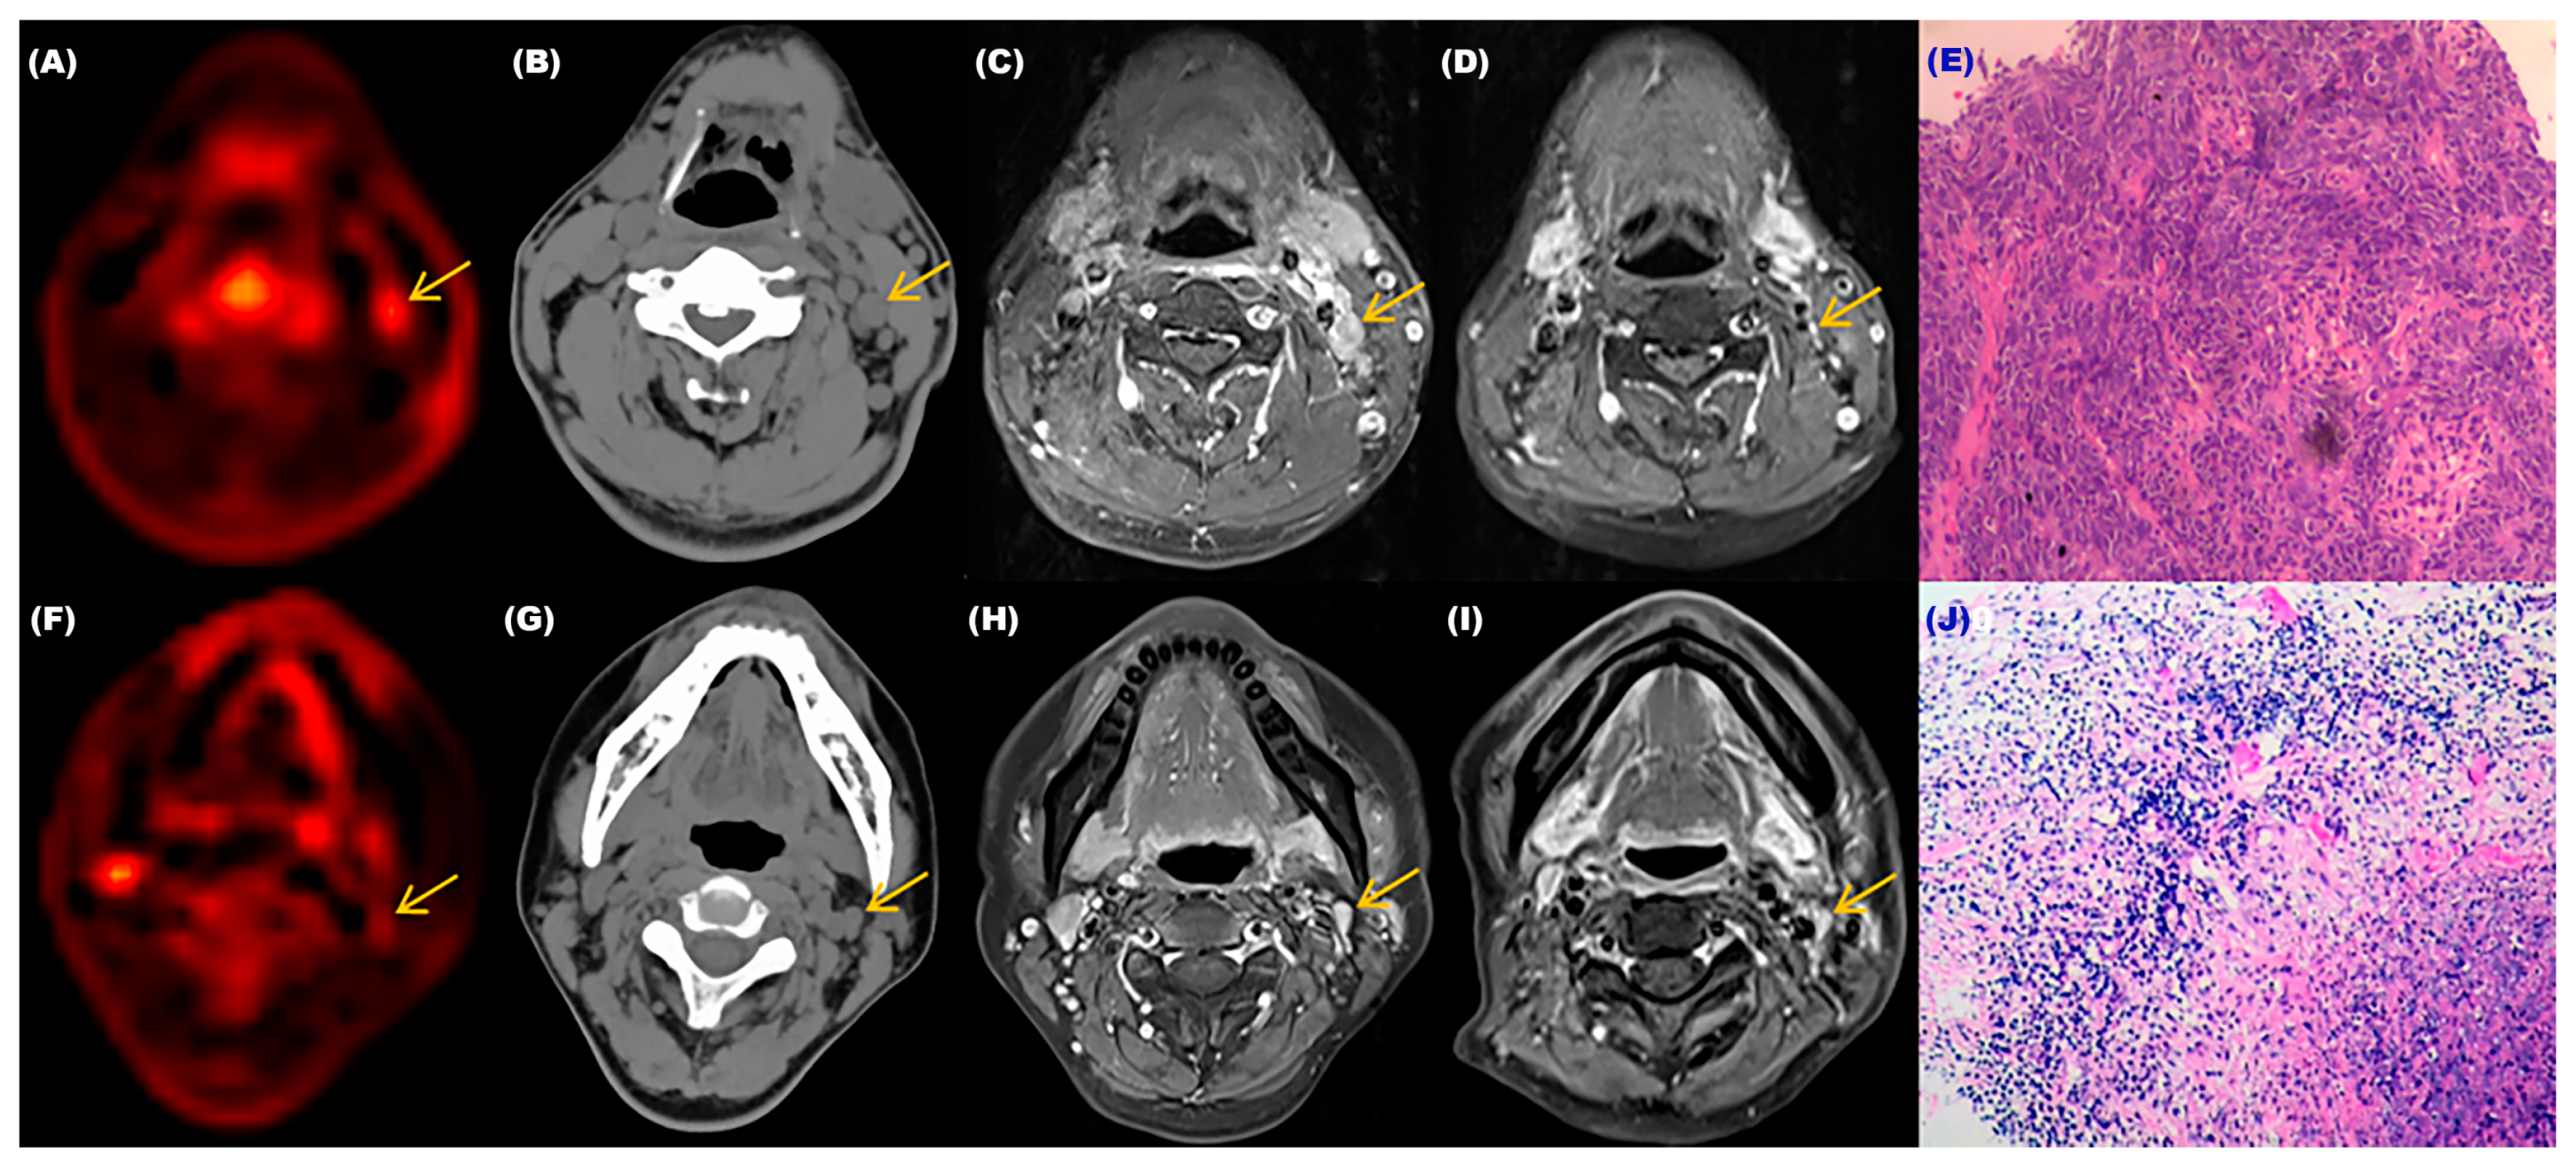

We selected two patients who underwent dynamic and static PET/CT scans and cervical lymph node biopsies before treatment and completed MRI examinations before and after treatment. The relevant results were shown in Figure 5. These two patients’ cervical lymph nodes were <1.0 cm in size before treatment, and both showed low metabolism (SUV-Max = 1.6) on static PET-CT. Without biopsies, their benign and malignant status could not be determined, and from the results in Figure 4, one of the individuals had a positive cervical lymph node biopsy result. From the MRI images before and after treatment, there was a significant change in the size of the cervical lymph node (>50%). The Ki-Mean was 0.01065, the Ki-Max was 0.01156, and the metabolism was elevated in dynamic PET CT images. On the contrary, the biopsy result of another patient was negative, and there was almost no change in the cervical lymph node before and after treatment. The Ki-Mean was 0.00658, the Ki-Max was 0.00749, and the metabolism was not obvious in dynamic PET-CT images. The Ki values of the malignant lymph node were significantly greater than that of the benign lymph node. This result indirectly indicated that dynamic PET-CT could be the best choice for low SUV values and sizes < 1.0 cm, which could not determine the nature of cervical lymph nodes.

Figure 5.

The relevant examination results of two patients with different cervical lymph nodes. (A) Dynamic PET-CT image of the patient with the malignant cervical lymph node. (B) CT image of the patient with the malignant cervical lymph node. (C,D) MRI images of the patient with the malignant cervical lymph node before and after treatment. (E) Pathological image of the patient’s lymph node which was confirmed as malignant. (F) Dynamic PET-CT image of the patient with the benign cervical lymph node. (G) CT image of the patient with the benign cervical lymph node. (H,I) MRI images of the patient with the benign cervical lymph node before and after treatment. (J) Pathological image of the patient’s lymph node that was confirmed as benign.